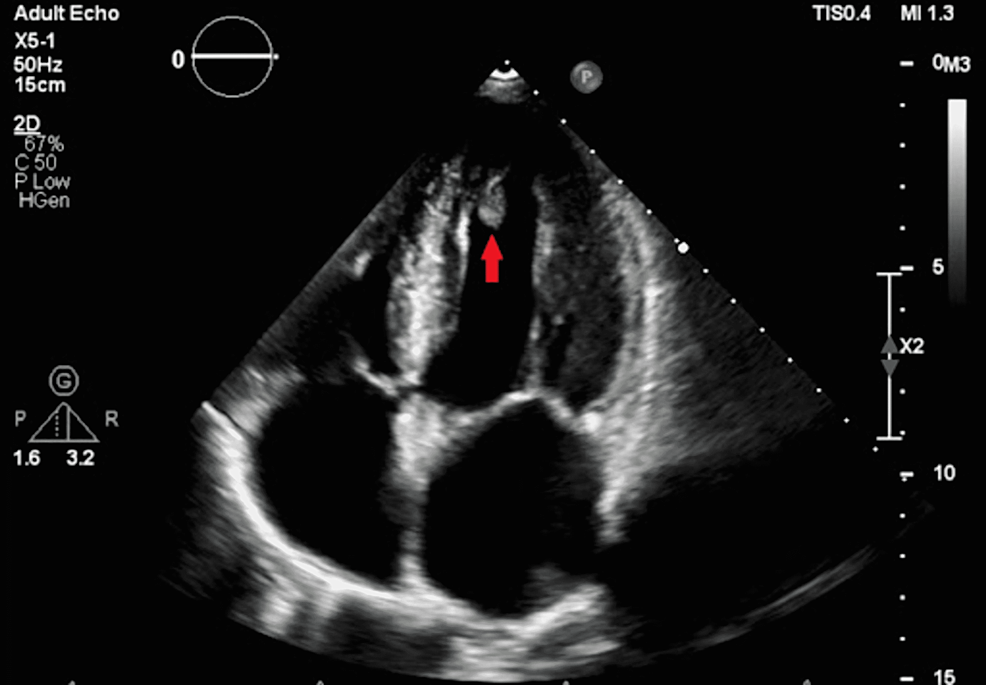

best cardiac doctors in bangalore An LV (left ventricular) clot in an echo is a blood clot tha An LV (left ventricular) clot in an echo is a blood clot that forms inside the heart's main pumping chamber, and it's often a complication of a heart attack. Echocardiography (echo) is the main diagnostic tool used to see it, though contrast-enhanced echo can improve accuracy. Diagnosis depends on seeing a distinct mass within the ventricle.